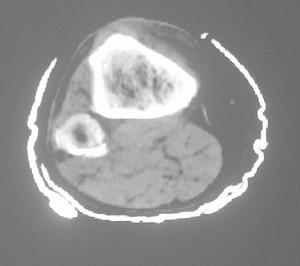

X線示左股部軟組織富血供性占位。鏡下所見:腫瘤細胞呈腺泡樣巢狀排列,瘤細胞大小不等,巢內緣不整,外周較圓滑,巢與巢之間為豐富的、互相連通的血管網。瘤細胞圓形、卵圓形或多角形,界清,胞漿豐富,有嗜酸性顆粒,核圓形,異型性小,含有核仁,核分裂象不易找到。